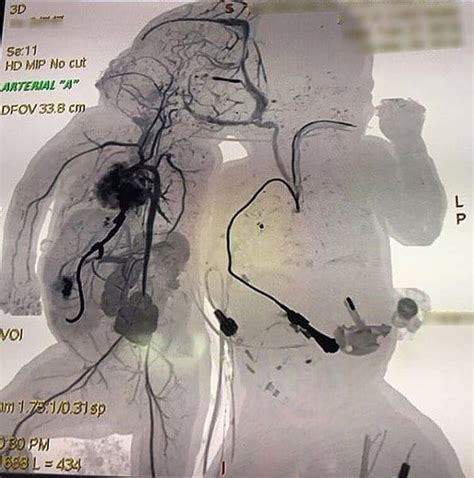

So, guys, not all conjoined twins are the same, right? The way they’re connected really varies, and this affects everything from their daily lives to potential medical interventions. Doctors have actually classified them based on where they are joined. The most common type is thoracopagus , where the twins are joined at the chest. They might share part of the sternum, abdomen, diaphragm, and sometimes even the heart. This is often the most challenging type for separation because of the shared vital organs, especially the heart. Then there are omphalopagus twins, who are joined at the abdomen, usually from the sternum down to the navel. They often share parts of the liver, intestines, and diaphragm, but their hearts are usually separate, which can make surgical separation more feasible than in thoracopagus cases. Another type is ischiopagus , where the twins are joined at the pelvis and share lower abdominal organs, rectum, and bladder. This type is often more difficult to separate due to the shared lower body structures and potential for significant functional impairment after separation. Less common types include pygopagus , joined at the back, and craniopagus , joined at the head. Craniopagus twins are particularly rare and present unique challenges because the head is such a sensitive area, often involving shared brain tissue or blood vessels, making separation extremely risky, if not impossible. The classification is super important because it guides the entire medical approach. Each type requires a tailored plan, considering the specific shared anatomy, potential risks, and the overall health of the twins. The medical team will meticulously map out the connections using advanced imaging techniques like MRI and CT scans to understand exactly what they’re dealing with. This detailed understanding is critical for planning any potential separation surgery, which is a massive undertaking. The decision to attempt separation is never taken lightly and involves extensive ethical considerations, weighing the potential benefits against the risks. Sometimes, separation isn’t medically possible or advisable, and the focus then shifts to ensuring the twins have the best possible quality of life together, with support for any associated health issues.

Dealing with conjoined twins presents some of the most complex medical challenges known. When we talk about surgical interventions, it’s often a journey filled with incredibly high stakes. The primary goal, when possible and deemed beneficial, is separation surgery . But this isn’t your average surgery, guys. It’s a highly specialized procedure that requires a massive team of surgeons, anesthesiologists, nurses, and support staff, often taking many hours, sometimes even days. The success and feasibility of separation hinge entirely on the specific anatomy of the conjoined twins. If they share vital organs like the heart, liver, or intestines, the risks escalate dramatically. Surgeons need to meticulously plan how to divide these shared organs, reconstruct them for each twin, and ensure they can function independently. Sometimes, separation isn’t possible, either because the risk is too high or because the twins cannot survive independently after the procedure. In such cases, the medical focus shifts to providing the best possible care for the twins as they are, managing any health complications, and ensuring their quality of life. Even when separation is successful, the twins face a long road of recovery and rehabilitation. They may require multiple follow-up surgeries to correct any lingering issues or to address developmental challenges. Beyond surgery, conjoined twins often have other medical conditions that need attention. These can range from congenital heart defects to gastrointestinal problems, orthopedic issues, and neurological complications. The lifelong care required is extensive, and it often involves a team of specialists monitoring their development and addressing their needs. The psychological and emotional support for the twins and their families is also a critical aspect of their care. It’s a testament to medical innovation and the dedication of healthcare professionals that many conjoined twins lead fulfilling lives, whether separated or together. The journey is always complex, but with advancements in medical technology and a compassionate approach, hope and positive outcomes are increasingly possible. It’s a constant learning process for the medical community, pushing the boundaries of what’s possible in reconstructive surgery and pediatric care. The resilience of these children and their families is truly remarkable to witness throughout this demanding process.